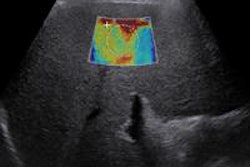

The main limitation to greater adoption of ultrasound has been the difficulty in training users, so the partnership will have an important impact worldwide, SonoSim said.